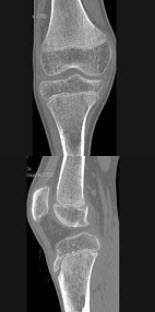

A.孤立圆形阴影

192、单项选择题

男,46岁,膝关节疼痛1年余,结合图像,最可能的诊断是()

A.骨质硬化

B.骨质疏松

C.骨质软化

D.骨髓瘤

E.转移瘤

点击查看答案